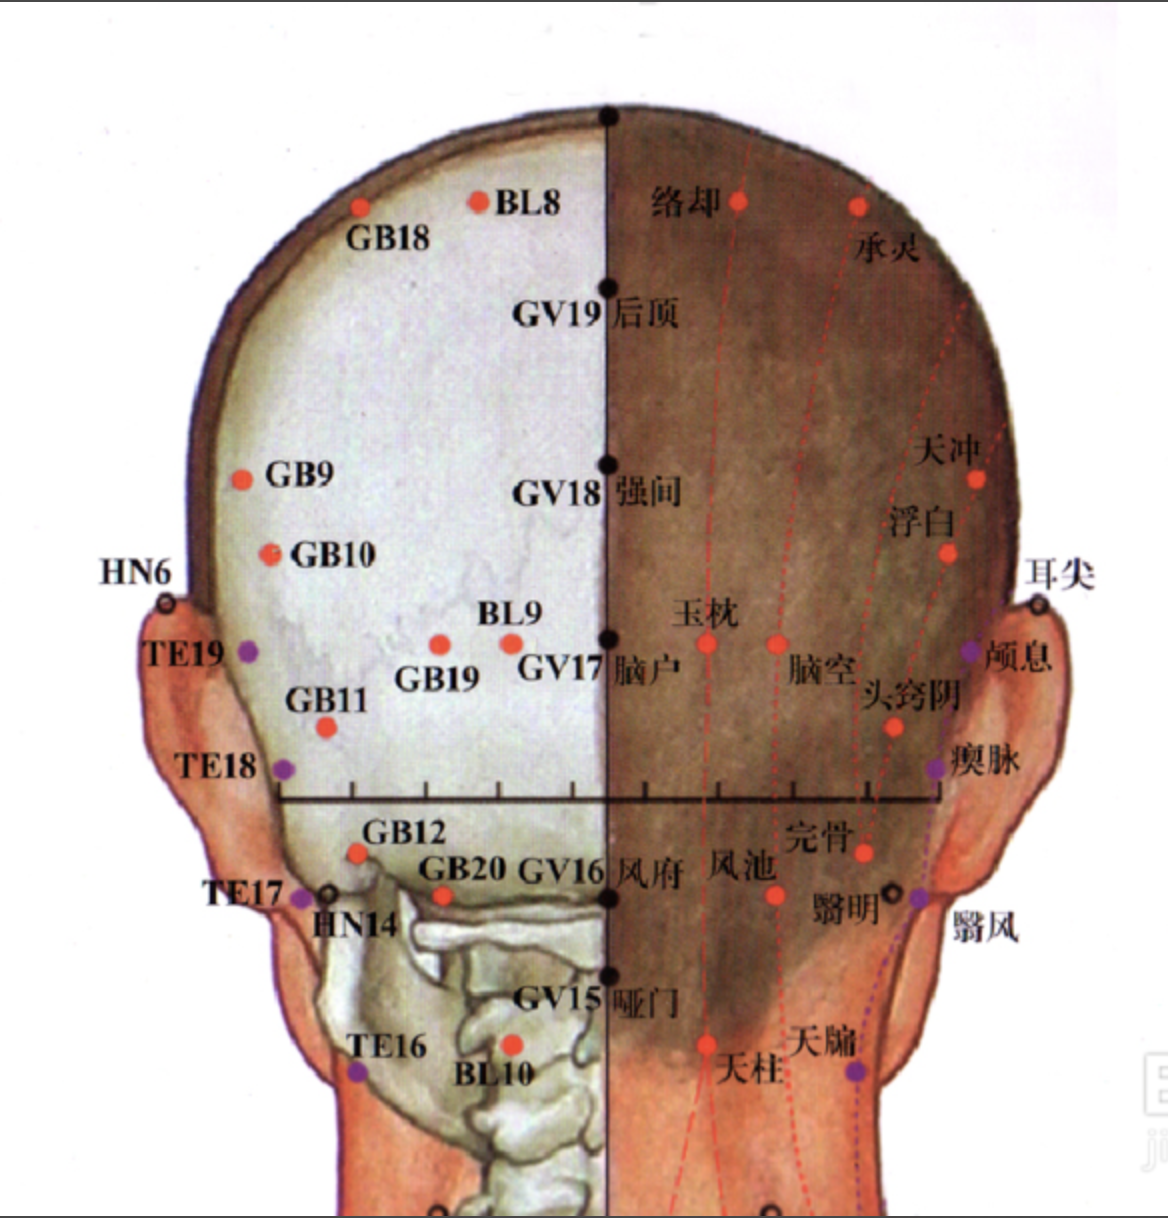

【(七)足太阳膀胱经(图 10-25-1)】

1、时辰 申时 15 ~ 17

2、歌诀 足太阳经六十七,精明目内红肉藏,攒竹眉冲与曲差,五处上寸半承光,通天络却玉枕昂,天柱后际大筋外,大杼(zhù)背部第二行,风门肺俞厥阴四,心俞督俞膈俞强,肝胆脾胃俱挨次。三焦肾气海大肠,关元小肠到膀胱,中膂(lǚ)白环仔细量,自从大杼至白环,各各节外寸半长,上髎次髎中复下,一空二空腰髁当,会阳阴尾骨外取,附分侠脊第三行,魄户膏肓与神堂。噫嘻膈关魂门九,阳纲意舍仍胃仓。肓门志室胞肓续,二十椎下秩边场,承扶臀横纹中央,殷门浮郗到委阳,委中合阳承筋是,承山飞扬踝附阳。昆仑仆参连申脉,金门京骨束骨忙,通谷至阴小指旁。

3、经脉循行 起于目内眦,上额交会于于巅顶(百会)。

巅顶部支脉:从头顶到颞(niè)颥(rú)部。

巅顶部直行的脉:从头顶入里联络于脑,回出分开下行项后,沿肩胛部内侧,夹脊柱,到达腰部,从脊旁肌肉进入体腔联络肾脏,属于膀胱。

腰部支脉:向下通过臀部,进入腘(guó)窝内。

后项部支脉:通过肩胛骨内缘直下,经过臀部下行,沿大腿后外侧与腰部下来的支脉会和于腘窝中。从此向下,出于外踝后,第五趾骨粗隆,至小指外侧端(至阴),与足少阴经相接。

4、主要病候 小便不通,遗尿,癫狂,疟疾,目痛,见风流泪,鼻塞多涕,鼻衄,头痛,项、背、臀部及下肢循行部位痛麻等。

3、主治概要 主治头、项、目、背、腰、下肢部病证及神志病,背部第一侧线的背俞穴及第二侧线相平的腧穴,主治与其相关的脏腑病证和有关的组织器官病证。

天柱

【定位】 在项部大筋(斜方肌)外缘之后发际凹陷中,约当后发际正中旁开 1.3 寸。

【主治】 头痛,项强,鼻塞,癫狂痫,肩背病,热病。

【配伍】 配大椎治头痛项强。

【刺灸法】 直刺或斜刺 0.5 ~ 0.8 寸,不可向内上方深刺,以免伤及延髓。